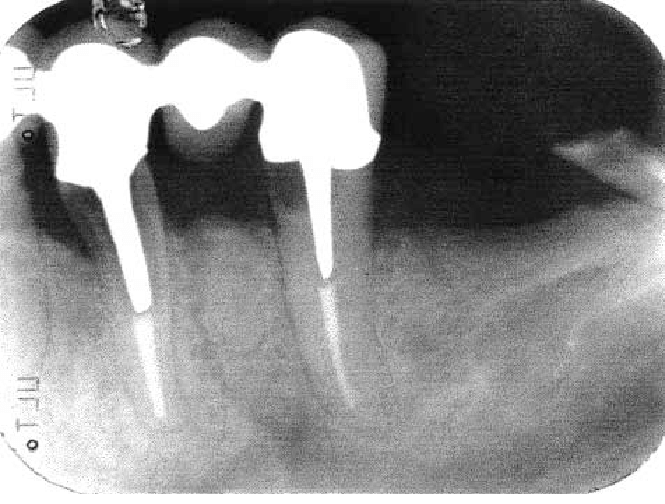

Question 21: What option is can be selected for distal tooth # 4.6?

Question 22: Which surface shows defective restoration?

Question 23: Which surface shows overhang?

Question 24: Which surface shows defective restoration?

Question 25: Which surface shows open margin?

Question 26: What option cannot be selected for mesial tooth surface # 2.8?

Question 27: What options cannot be seen in this X ray?

Question 28: What is the best option that describe distal surface of tooth # 3.5?

Question 29: What options cannot be seen in this X ray?

Question 30: What options can be selected for the tooth # 4.2?